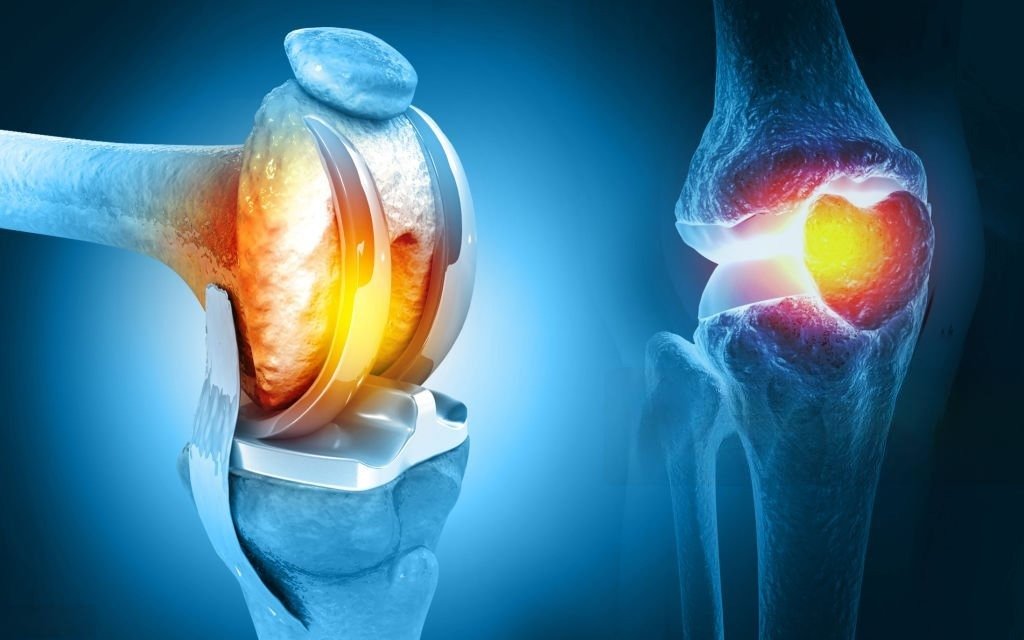

TOTAL KNEE REPLACEMENT

Read More -